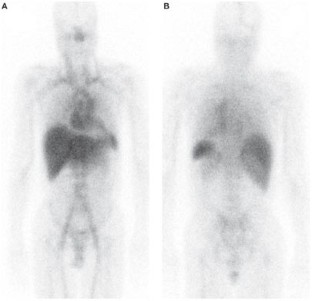

Investigations Electrocardiography, echocardiography, cardiac biopsy, measurement of serum levels of free light chain, scintigraphy with radiolabeled serum amyloid P component, transthyretin gene sequencing and immunohistochemistry.

Diagnosis Cardiac acquired monoclonal immunoglobulin-light-chain amyloidosis with the incidental presence of the amyloidogenic transthyretin Val122Ile mutation.